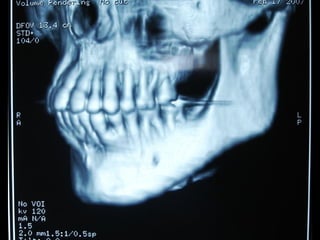

En el estudio radiográfico determinamos que el factor causal fué un foco séptico

dentario a nivel de segundo molar inferior izquierdo.